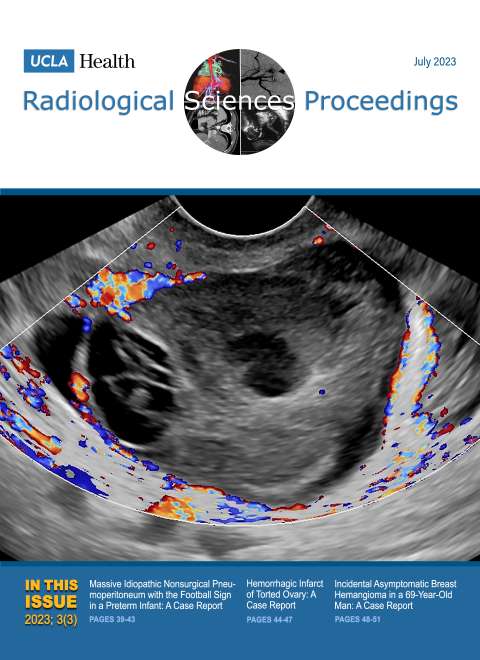

January 2023

Volume 3, Issue 1

- Concurrent Malignant Infantile Osteopetrosis and Hypophosphatasia in a Six-year-old Boy: A Case Report

- A Case Report: Colonic Atresia in a Newborn with Presumed Rubinstein-Taybi Syndrome

- Unilateral Hypertrophy of Tensor Fasciae Latae: A Report of Two Cases

- The Many Faces of COVID-19-Associated Cerebrovascular Disease: A Case Series